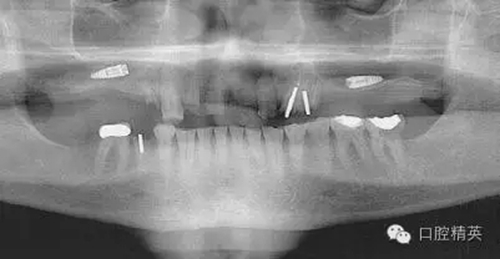

圖2a:術(shù)后曲面斷層片顯示兩顆種植體分別異位于左右側(cè)上頜竇中

圖4:兩維曲面斷層影像難以獲得精確定位,有的醫(yī)生為了避免損傷下頜神經(jīng)管而應(yīng)用短種植體。這樣做的結(jié)果是增加了修復(fù)體-種植體長(zhǎng)度比,隨著時(shí)間的流逝會(huì)造成骨吸收,最終可能導(dǎo)致種植體折斷。骨內(nèi)折斷的種植體片斷需要手術(shù)取出,然后進(jìn)行植骨,骨質(zhì)愈合后再次種植,這些步驟不僅創(chuàng)傷大,而其從心理和經(jīng)濟(jì)上都會(huì)對(duì)患者造成損失。

圖7a:6,7號(hào)牙種植體(3*15mm)折斷前,從物理學(xué)理論上講,種植體骨整合后,基臺(tái)螺絲和種植體相連接的支點(diǎn)處是受力時(shí)種植體最薄弱的位置。(a)可見6號(hào)牙種植體的折斷面,和7號(hào)牙種植體上的折裂線(b)

圖7b:6,7號(hào)牙種植體折斷后。

圖7c,d:6,7號(hào)牙的回顧性模型分析顯示為了獲得滿意的美學(xué)效果牙冠不得不做的很長(zhǎng),從而形成較深的咬合關(guān)系。同時(shí)可見對(duì)

頜牙磨耗嚴(yán)重,廣泛。